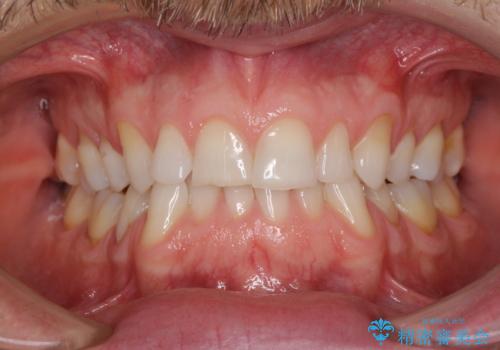

インビザラインチェンジで成功 インビザラインで八重歯の抜歯矯正

前歯が気になる 大人のマウスピース矯正 矮小歯を整える

出っ歯 下の歯のガタガタ 下の前歯のみ1本抜歯 マウスピースで1年